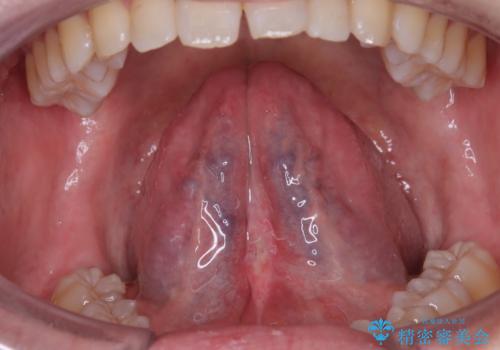

小帯の形成術によって舌の可動域が広がりました。

舌小帯形成術は、舌の下にある小帯(舌小帯)を調整する手術です。通常、舌小帯が短い場合に行われます。この手術は、滑舌の改善や発音の向上に使用されます。